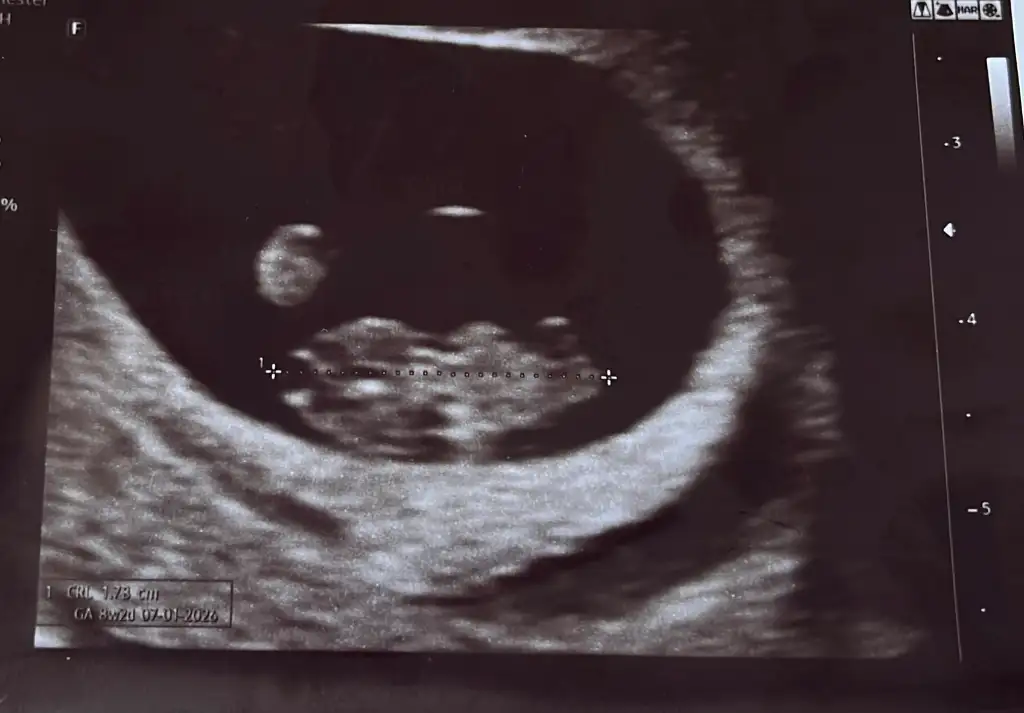

8+3 karından ultrasonla çekildi cinsiyet tahmini yapabilecek var mı